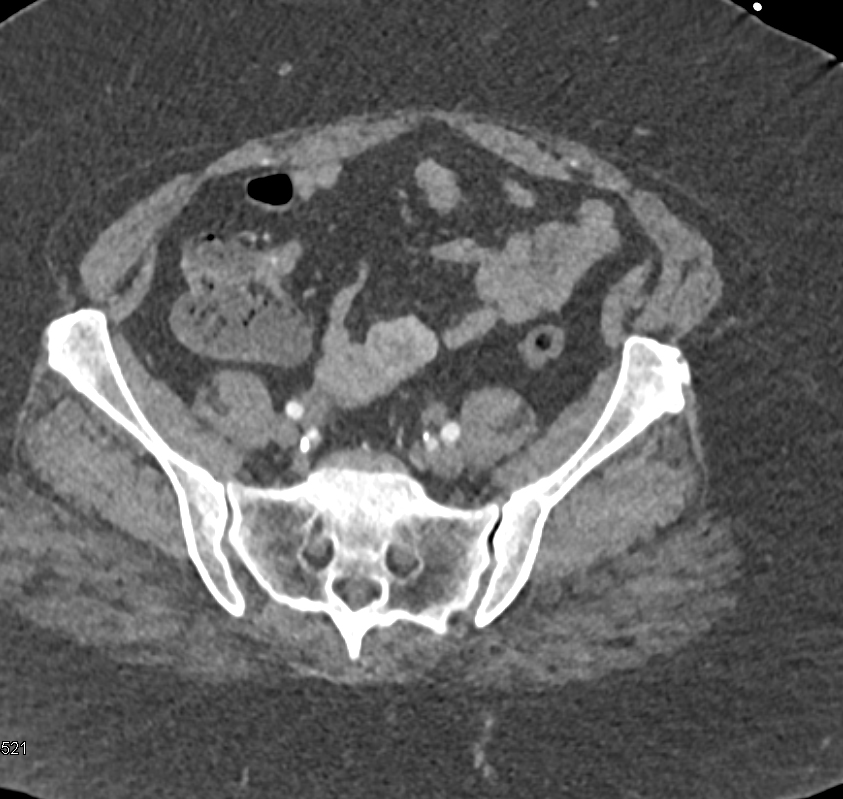

1) The CT finding in the abdominal wall is best known as?

herniation of small bowel

abscess

Sister Mary Joseph nodule

metastatic disease